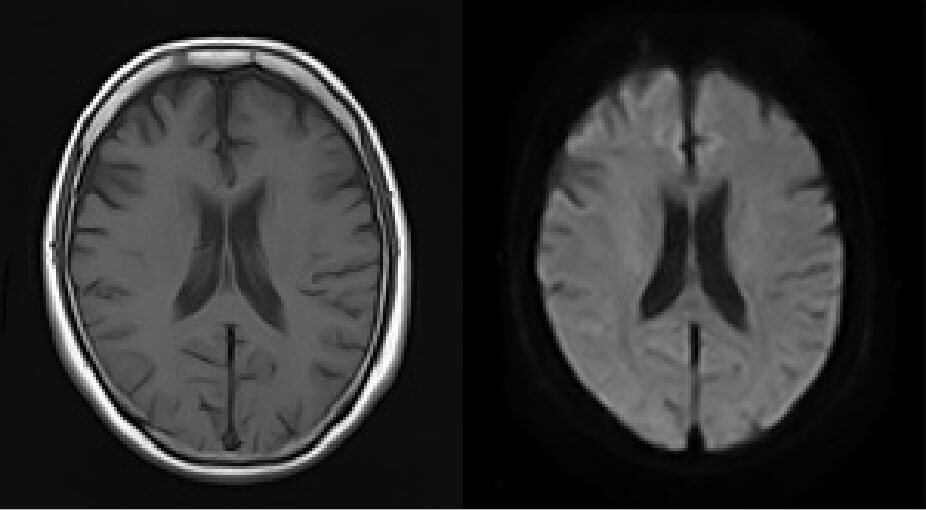

正常な脳のMRI画像1